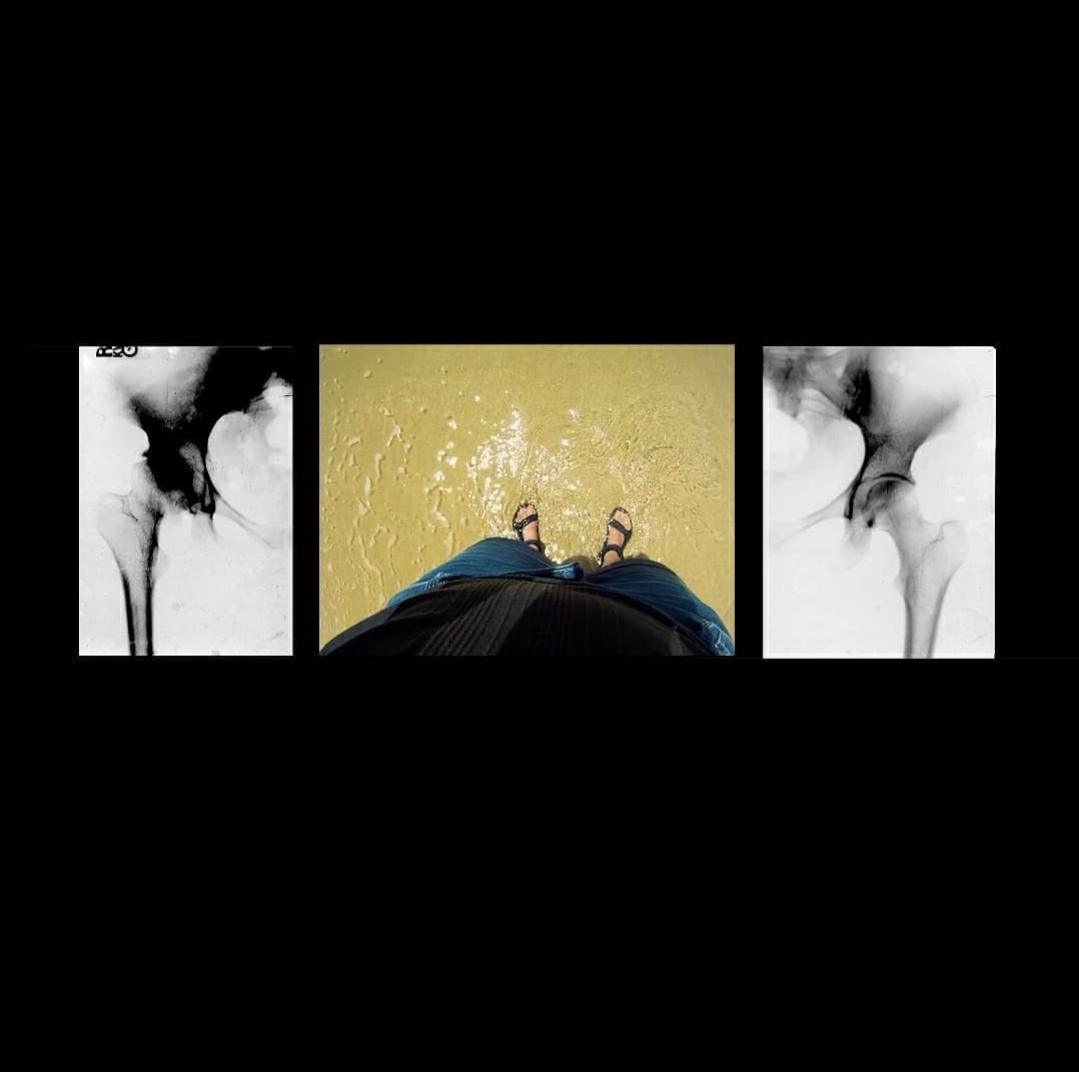

베토벤이 그의 장애를 포용하면서 중기 또는 영웅시기에 했던 작곡은 클래식 음악에 혁명을 일으켰습니다. 베토벤의 두려움과 자기 고립은 저또한 깊이 이해하는 경험입니다. 맨 처음 이동성 장애가 있다는 진단을 받았을 때 (추후 자가면역질환으로 인한 것임을 알게 되었습니다) 저는 장애를 숨기고 몸이 다르게 움직이는 것에 대한 수치심을 내면화하는 데 수년을 보냈습니다. 이것은 또한 저를 고립되게 만들었습니다. 시간이 지남에 따라 예술을 통해 저의 고유함에 자부심을 갖는 법을 배웠습니다. 이 작품의 영상은 2011년 촬영한 것으로 제가 고관절 치환 수술 전후 79 일 동안 걷는 모습입니다. 79일의 촬영분 중 8개의 동영상을 저의 장애를 드러내는 첫 전시회에 공개하였습니다.

(걷는 모습을 담은) 비디오 아카이브를 다시 방문하면서 저는 제 몸의 움직임을 음악처럼, 이동 보조기구를 악기로, 다양한 걷는 방법과 박자를 교향곡이라 생각할 수 있었습니다.